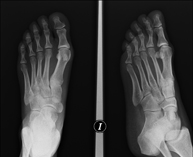

- Limb X-ray

This technique uses X-ray imaging to examine the limbs, especially the bones. Indicated for: trauma, joint infections.